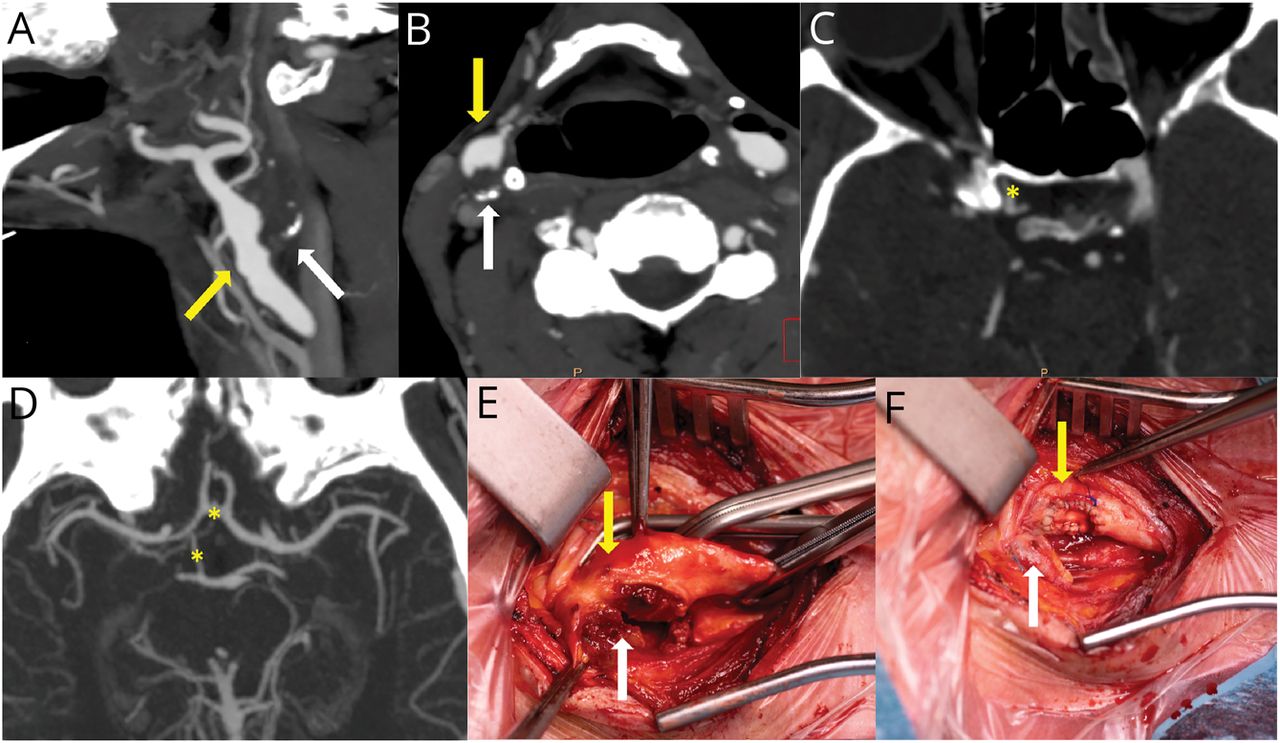

图2 CT血管造影术和术中图像

矢状轴向(A)和(B) CT血管造影显示一个管腔内的血栓在原点的ECA(黄色箭头),而颅外的ICA完全闭塞(白色箭头)。脑血流量的supraclinoid段右颈内动脉及其分支是由侧枝循环(黄色星号),即眼动脉(C),前动脉,交流和沟通后动脉(D),手术切口在颈内动脉球显示脂质斑块导致完整的ICA闭塞(白色箭头)和部分遮挡的ECA(黄色箭头)和CCA (E),执行一个动脉内膜切除术,然后用涤纶动脉被修复补丁,不包括非功能性ICA (F)。CCA =颈总动脉;ECA =颈外动脉;ICA =颈内动脉。